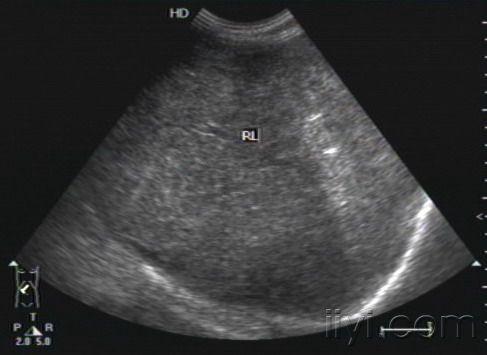

超声所见:肝脏体积明显增大,下界平脐.